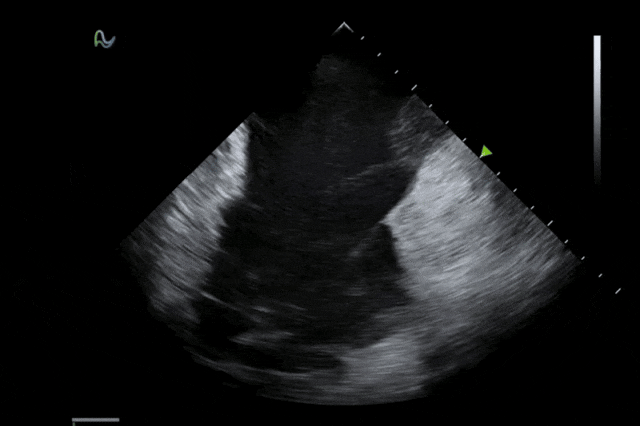

本次获批的ICE导管在全球首次采用了80阵元大孔径高密度探头设计,较传统普通的64阵元产品大幅度提升了成像分辨率、成像深度和图像对比度,可清晰辨识心脏细微结构和血流,为复杂手术提供更可靠的超声成像支持。同时,8F导管凭借更小的外径,显著提升导管通过性和操控性,对病人创伤更小,尤其适合血管条件受限或小心脏患者;10F导管则凭借其优质的成像质量,为复杂心脏介入手术提供精准的影像引导。